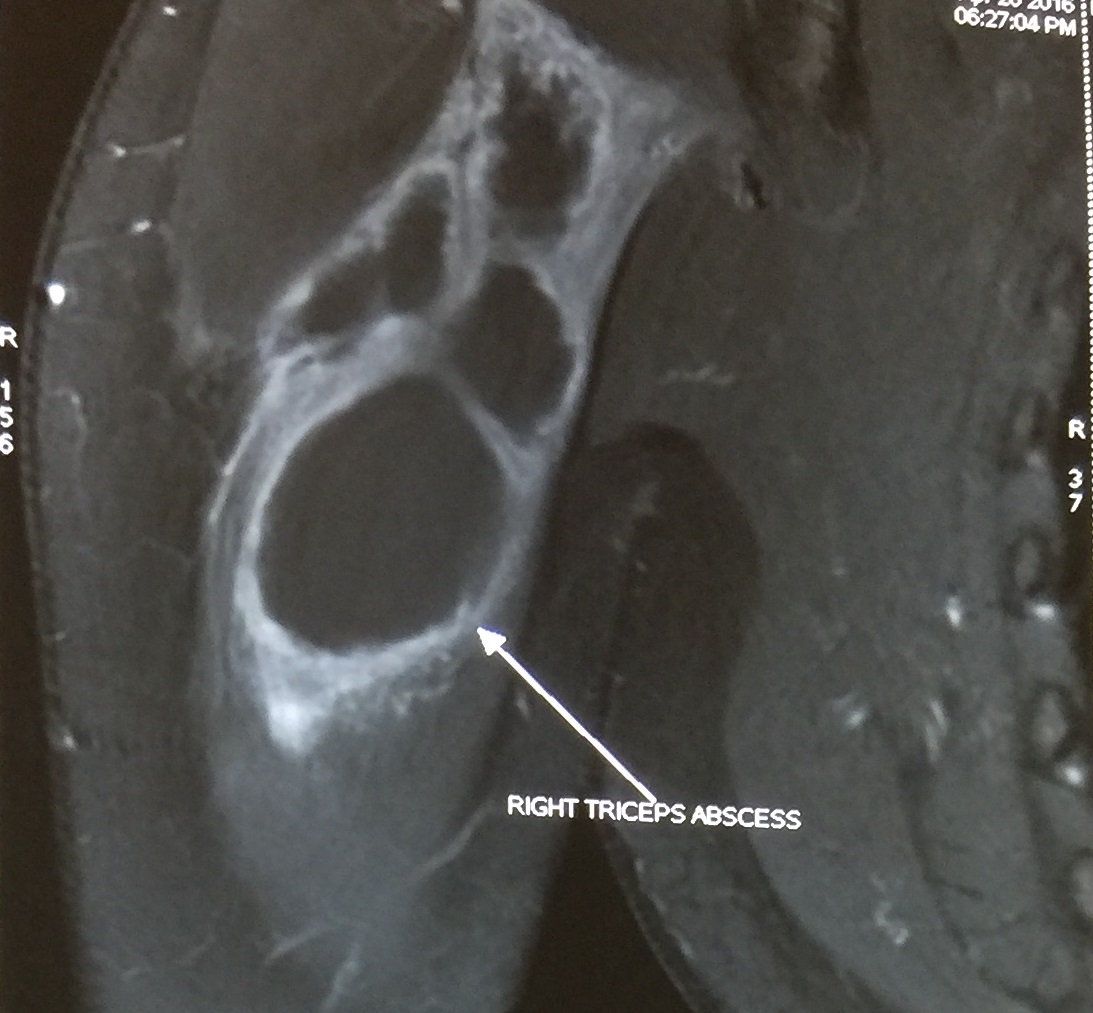

A 23 year old female was referred to us in April 2016 with right shoulder swelling for 3 months. In January 2015 she had fever and right axillary lymphadenopathy and was diagnosed to have right forearm cysticercosis as her MRI of the right shoulder showed ruptured cysticercal granuloma in the distal triceps. MRI brain at that time was normal. She was treated with Albendazole at that time. The duration of Albendazole is not known. Her brother was also diagnosed with neurocysticercosis in January 2016. The family used to eat a vegetarian diet. In January 2016, due to a repeat swelling in right shoulder, immunological workup was done. Her serum IgG was 952 gm/dl, IgM was 248 gm/dl and IgA was 309 gm/dl. At presentation in April 2016 she had a non-tender right upper arm swelling. MRI of the right shoulder showed a large loculated abscess involving proximal triceps (size 8.8x2.7x3.5 cm) and proximal tibia (figure 1). The fluid in the distal triceps that was seen in the Jan 2015 imaging had resolved. She was restarted on Albendazole and advised to do Cysticercus Elisa IgM and IgG, stool examination and further immunodeficiency workup in form of HIV and lymphocyte subset analysis. She was also advised surgical excision of the abscess.

Figure 1: MRI of right shoulder shows large loculated abscess involving proximal triceps and proximal tibia